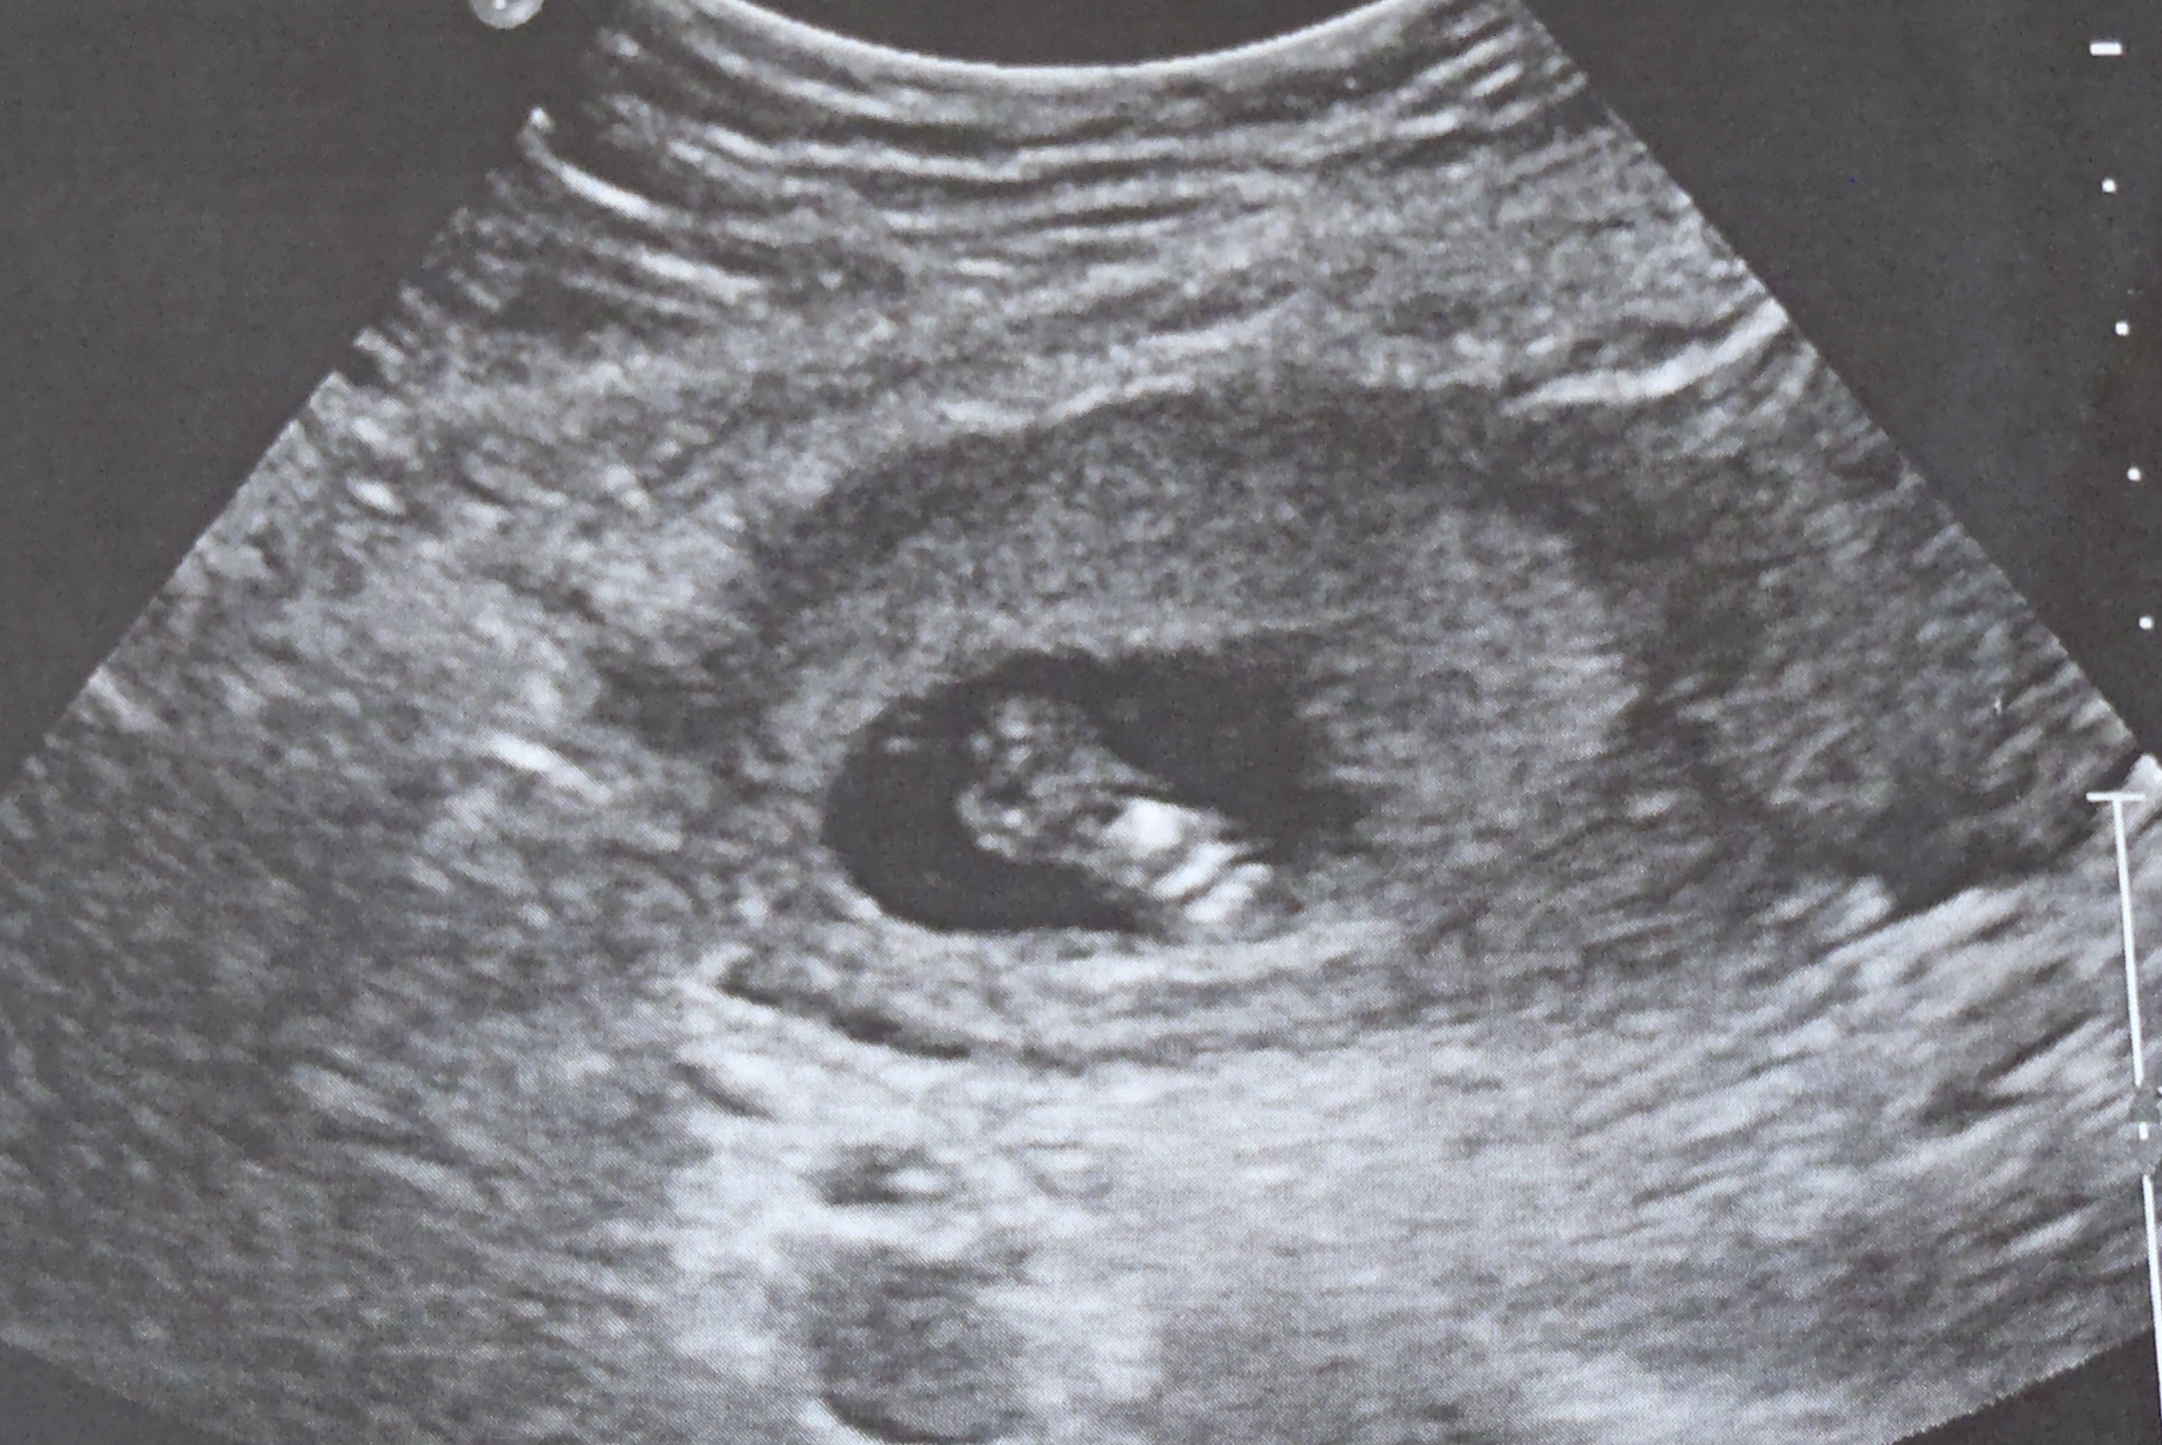

Here's our story...We lost our baby girl at 16 weeks gestation. We started 2013 with a cruise to get one last vacation in before starting a family. When we returned, we got pregnant right away. We were so excited. The excitment quickly turned into hesitation the day after the first Doctor's appointment. A subchorionic hematoma caused bleeding and during the ultrasound, a uternine septum was also discovered. The baby was fine, but the spetum was a scary discovery. Typically septums can problems in the first trimester (a miscarriage) or in the third trimester (breeched, early labor) so we had extra monitoring. Septums can be removed, but that can not be done while pregnant. Everything was still going well at the 12 week appointment, so we thought we were in the clear. We started dreaming about who this baby would be, planning the nursery and thinking of names. Our world crumbled when we learned our baby no longer had a heartbeat at our 16 week appointment. We later learned that the septum was extremely large and I had a blood clotting disorder, both of which could have contributed to the miscarriage. Over the next year, I underwent three surgeries to remove the septum, and a plan was in place for me to be on blood thinners during all future pregnancies. The surgeries and blood thinners were successful, giving us two boys. We will always wonder who our baby girl, Gabriel, would have been. Do her brothers look like she would have? What would she have thought about her brothers? Would she have grown up to be a swimmer or played hockey? Would she have loved the cats or would she have begged us for a dog? Would her eyes have been as big and brown as her mom's? Would her hair have been thick and dark like her dad's? She was first a dream, then a reality and now a memory.